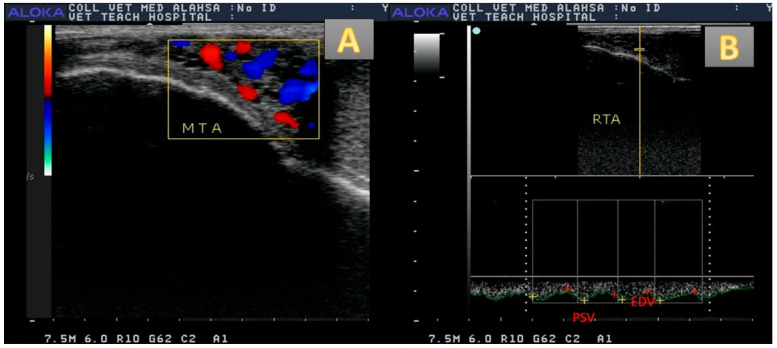

This study aims to demonstrate whether immunization against inhibin could alters testicular echotexture (TE), hemodynamics (resistance and pulstalilty index [RI and PI], testicular blood flow volume [TBFV]), and semen picture. Senile male camels were immunized actively against inhibin alpha subunit (immunized males; n = 5; subcutaneous route; 1 mL) or non immunized (control males; n = 5). The injection was four times with four weeks intervals. Semen was collected by electroejaculator once per week. Blood sampling, ultrasonography, and hormonal assaying was performed once per week. The levels of follicle stimulating hormone (FSH), luteinizing hormone (LH), estradiol (E2), testosterone (T), and nitric oxide (NO) were calculated. Regarding control camels, the FSH levels were elevated (p < 0.01) in immunized males weeks 6-9 in August. Both E2 and NO were increased in the same group at weeks 7-11 with the highest level in week 10 for E2 (17.01 ± 0.11 pg/mL) in September and in week 9 for NO (44.66 ± 0.15 µmol/L). The Doppler indices RI and PI were declined (p < 0.01) in immunized camels in weeks 7-11, while the TBFV was elevated (p < 0.01). A marked elevation (p < 0.05) in testicular volume was noticed in the immunized group with a decline in the TE in week 9. The sperm cell concentration and viability were elevated (p < 0.01) in the immunized group. In conclusion, the active immunization against inhibin in senile camels shows a positive effect via improvement of testicular hemodynamics, flow volume, testicular volume, FSH, E2, NO, and sperm cell concentration with viability %, and alterations in both Doppler indices with the TE.

本研究旨在探讨免疫抑制素是否会改变睾丸超声图(TE)、血流动力学(阻力和脉搏指数[RI和PI]、睾丸血流量[TBFV])和精液图像。对老年雄性骆驼主动免疫抑制素α亚基(免疫雄性,n = 5;皮下途径,1 mL)或未免疫(对照雄性,n = 5)。注射四次,间隔四周。每周用电射精器采集一次精液。每周进行一次血液采样、超声检查和激素检测。计算促卵泡激素(FSH)、黄体生成素(LH)、雌二醇(E2)、睾酮(T)、一氧化氮(NO)水平。与对照骆驼相比,8月6-9周接种的雄性FSH水平升高(p < 0.01)。同一组E2和NO均在7-11周升高,E2在第10周最高(17.01±0.11 pg/mL), NO在第9周最高(44.66±0.15µmol/L)。免疫后7 ~ 11周,多普勒指数RI和PI下降(p < 0.01), TBFV升高(p < 0.01)。免疫组在第9周睾丸体积显著升高(p < 0.05), TE下降。免疫组小鼠精子细胞浓度和活力显著升高(p < 0.01)。综上所述,抑制素主动免疫对老年骆驼的睾丸血流动力学、睾丸流量、睾丸体积、FSH、E2、NO和精子活力%浓度的改善以及与TE相关的两种多普勒指数的改变均有积极作用。